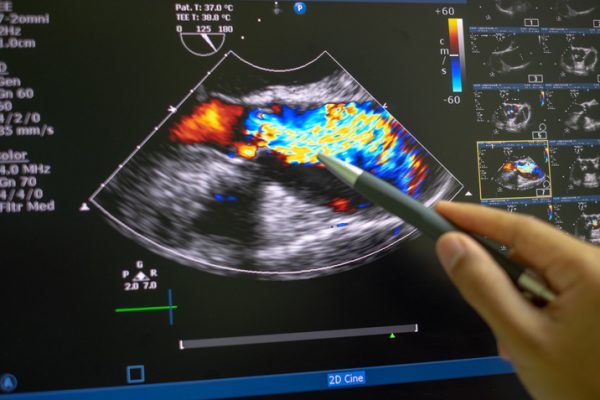

Color Doppler u ginekologiji